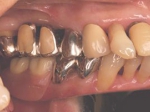

インセラム(オールセラミック)症例②

治療前治療前術前 治療後治療後術後 歯の尖端の透明感までよく再現できている。